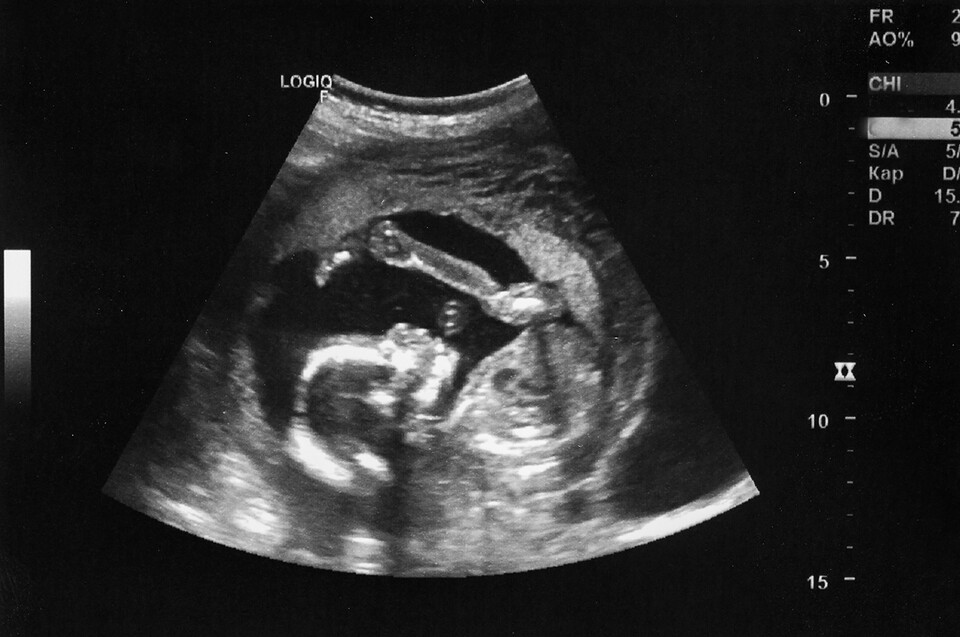

만삭인 임신 36주 차에 인공임신중절(낙태) 수술을 받았다는 유튜브 영상과 관련, 서울시의사회는 “철저한 사실관계 확인”을 요구했다. 사실이라면 낙태 수술을 한 의료진을 처벌해야 한다고 했다.

서울시의사회는 16일 성명을 내고 엄정한 수사를 촉구하며 이같이 말했다. 서울시의사회는 36주 차에 낙태 수술을 했다는 의혹이 사실로 밝혀지면 “전문가평가단 등 철저한 조사를 통해 자체적으로 강력한 징계 조치를 내리겠다”고 강조했다. 서울시의사회는 지난 2019년부터 전문가평가단을 운영하고 있다.